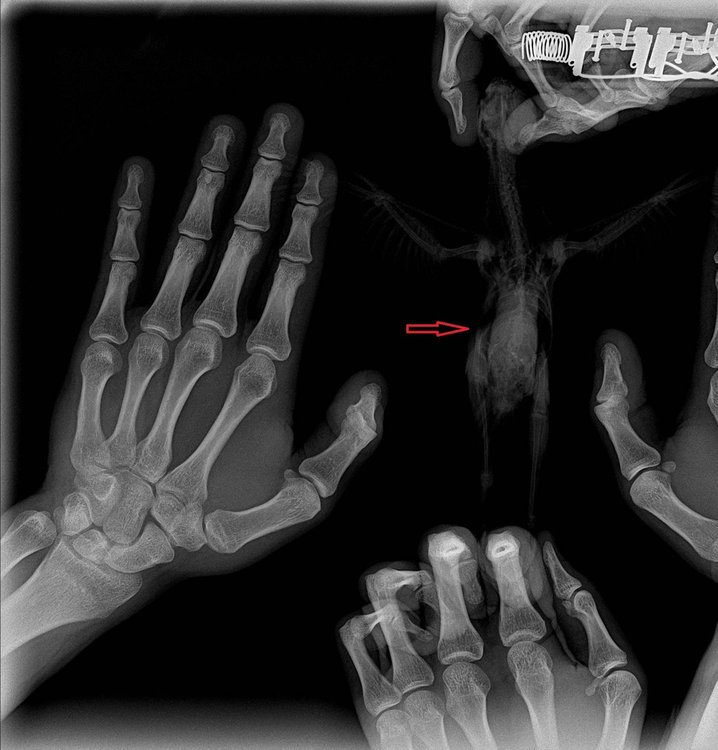

В общем в ветеринарке при нас принесли птенца какарика на услыпление, в ходе разговора выяснили что проблема в лапке. Нам стало его жалко и решили взять себе. Думали вывих. В итоге с горем пополоам записались на прием к орнитологу по совместительству, и на рентгене уже поняли, что у птенца закрытый перелом правой шейки бедра (фото прилагаю). Из информации которая есть - птенцу 28 дней, травма была получена, как нам сказали 8 дней назад. Прошлые хозяева никак не лечили, насколько я понял. Аппетит у птенца хороший, кормим немолочной 5 злаковой кашей хайнц, пробуем давать вареную морковь. Ведет себя бодро. кал нормальный (не жидкий и не твердый) зеленого цвета. В районе травмы опухлость, кожа равномерно бордового цвета (сфоткать возможности сейчас нету, но там никаких отличающихся очагов чего либо или отличий по цвету нету), кожа тепленькая, синюшности и холода нету. Нерв, судя по всему не сильно пострадал, потому что пальчики сжимает, но слабо. Самой лапкой пошевеливает, насколько это получается возможным. Врач нам дал Мелоксидил 1.5 мг и Байтрил 2.5%, дополнительно сами с кашей даем кальция глюконат (посоветовали). Собственно вопрос - на что нам можно надеяться в данной ситуации? Есть шанс, что лапка как нибудь заживет и птица, пусть хромая, но сможет жить, или она все время будет испытывать сильную боль? Операцию по костям (резекция вроде) как в нашем случае у нас в городе (Ижевск) не делают - нет квалифицированных специалистов. Поковырять могут, но результат не гарантируют и все с большими оговорками и кучей "если". Очень надеюсь на ваш ответ, потому что мы в тупике и помощи от местных ветеринаров широкопрофильников получить не можем.

6t-k-_aRLps.jpg

REeKV36qOQE.jpg

z5l-BG2-HEs.jpg

Попробовали сделать фото кожи в месте травмы. Если очень надо, можем переделать. Из того что заметил сегодня - со стороны больной лапки снизу тоже какой то выступ, которого со стороны здоровой лапки нету. Птенца держим в коробке с опилом и больная лапка все время в таком положении. Первый день пробовали навязать какое то подобие бандажа, зафиксировать бедро, но как сказал врач и как сам уже почитал, смысла в нем в данной ситуации нет. Или есть?

купили травма-гель, намазали. в районе бедра гематома темного цвета и бедренная кость упирается в кожу.

Перелом бедра - это самый плохой перелом, т.к. его не зафиксировать и учитывая возраст и вес птицы даже не прооперировать (не у вас, а в Москве).

Ну , и в Москве у такого малыша никто остеосинтез не сможет сделать... НЕт таких спиц, а серкляжный шов на столь высокое место перелома- не наложить.

Лена,там был перелом,который невозможно скомпенсировать.

Если бы птица была взрослая и клинически здоровая- то такие спецы как Томашевский или Бугаенко может и смогли бы провести операцию остесинтеза

А такой малыш,которому и наркоз не дать, и фиксация невозможна, и ампутация... уж очень место сложное, прямо тазовые косточки, и кусочек бедренной кости маленький и с очень острыми краями...и не в Москве...

Он прорвал мягкие ткани, вероятнее всего вызвал обильнео внутреннее кровотечение.

Жить с таким невозможно.